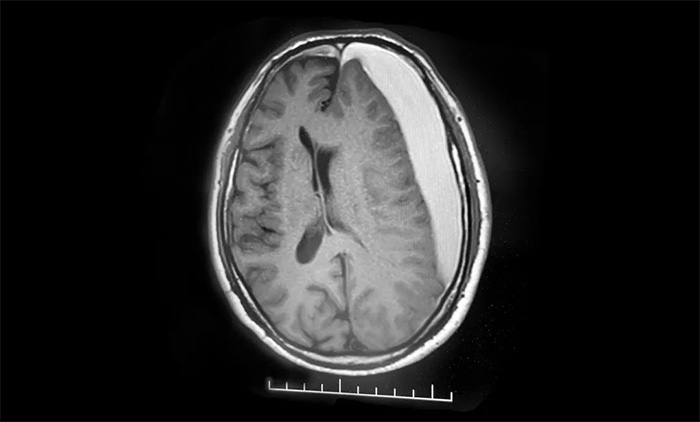

患者為老年男性。2023年12月25日中午突發(fā)言語不清,無流涎,無吞咽困難,無意識(shí)不清,當(dāng)時(shí)未重視。兩天后,病情加重,突發(fā)右側(cè)肢體活動(dòng)不利,摔倒,伴頭暈不適,無視物模糊,無天旋地轉(zhuǎn),無惡心嘔吐,無四肢麻木。經(jīng)磁共振檢查,診斷為左側(cè)額顳頂部及右側(cè)額部慢性硬膜下血腫。

▲ 左側(cè)額顳頂部及右側(cè)額部慢性硬膜下血腫,并擠壓腦組織導(dǎo)致中線右偏